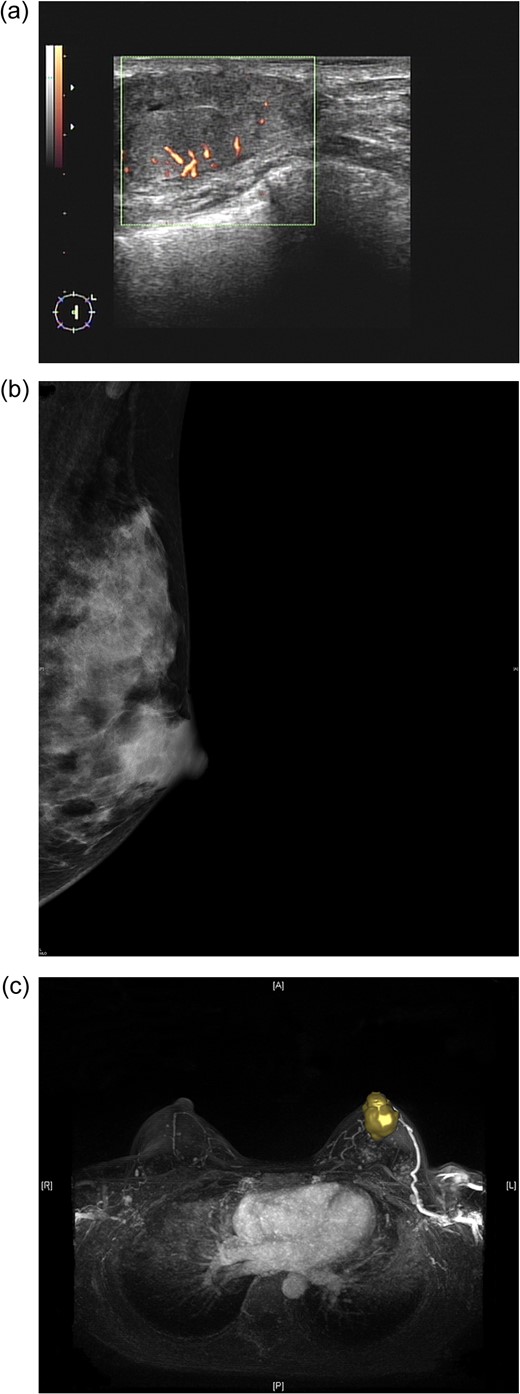

(a) Sonogram of the left breast reveals a 3.5-cm hypoechoic lesion with increased vascularity in the 2 o'clock/1-cm region. (b) Mammogram (mediolateral-oblique view) of the left breast shows a well-defined sharply circumscribed mass. (c) A maximal intensity projection magnetic resonance imaging image of the left breast revealed a 4.0-cm well-defined tumour with an engorged drainage vein beneath the nipple areolar complex region.

Preoperative mammography revealed one well-defined, sharply circumscribed lesion (Fig. 1b). Magnetic resonance imaging (MRI) showed one 4-cm circumscribed mass beneath the nipple-areolar complex (NAC) region of the left breast, with focal haemorrhage, nipple retraction, skin thickening, dilated ducts and lymphadenopathy (Fig. 1c).

Imaging studies may suggest characteristics of carcinomas arising from fibroadenomas [14–16]. In sonographic examination of fibroadenomas, irregular shape and contour, extensive hypo-echogenicity, shadowing, echogenic halo and distortion of surrounding tissue are considered to be hints of suspicious malignancy [15]. On mammography, irregular shape, ill-defined spiculated margins or pleomorphic/linear micro-calcifications should also be considered signs of malignancy [14]. With dynamic MRI, benign fibroadenoma and DCIS/IDC can be differentiated according to differences in vascularity [16]. Parameter colour maps can also demonstrate the extent of DCIS within a fibroadenoma [16]. However, in the case described here, sonography, mammography and MRI revealed a well-defined, sharply circumscribed hypoechoic lesion with increased vascularity (Fig. 1a–c). Preoperative imaging to differentiate benign from malignant fibroadenoma was not easy, and CNB was therefore performed to obtain a tissue diagnosis.